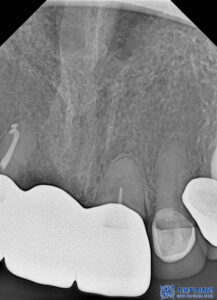

오른쪽 앞니는 이미 기존에 신경치료를 진행하여,

이에 따라 재신경치료를 진행하기로 하였습니다.

재신경치료는 이미 신경치료를 한번 했던 곳에

또다시 신경치료를 진행하는 것이기에

일반적인 신경치료보다 까다로워서

의료진의 실력이 중요합니다.

본원에서는

MTA 신경치료를 진행하고 있습니다.

본원은 MTA라는 바이오세라믹 성분을 사용하여

신경치료를 하고 있습니다.